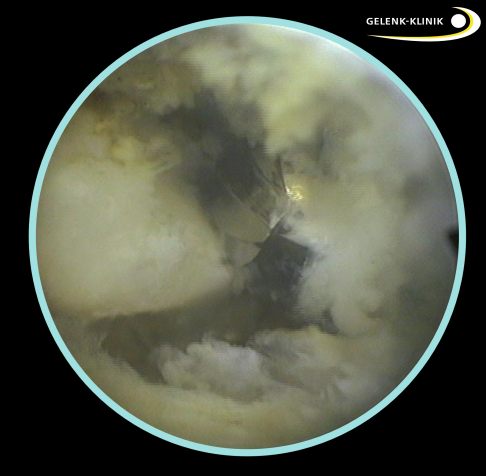

Unter Röntgenkontrolle mit einer beweglichen Röntgenröhre (Bildwandler) lokalisiert der Fußspezialist den Fersensporn und markiert ihn mit einer Nadel. Dann führt er über zwei kleine Hautschnitte eine Kamera mit Lichtquelle und spezielle chirurgische Instrumente ein. Durch die Nadelmarkierung kann der Fersensporn leicht gefunden und dargestellt werden. Mit einer kleinen Kugelfräse entfernt der Operateur den knöchernen Vorsprung. Dann glättet er das Fersenbein vollständig, um eine weitere Reizung und Entzündung der Sehnen zu verhindern.

Abtragung des Fersensporns: Nach der Markierung bringt der Operateur eine Fräse ein, mit der er den Knochenanbau schonend abträgt. © Gelenk-Klinik